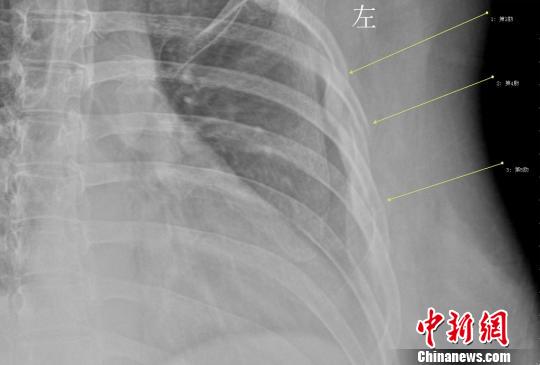

第 9 肋骨 骨折-肋骨の全体的な骨折では前述した通り第4肋骨~第8肋骨の骨折が多くなります。 しかし、ゴルフや野球のスイングなどによる疲労骨折のケースでは第4肋骨~第8肋骨だけでなく 第1肋骨 第2肋骨 の2箇所も疲労骨折を生じやすくなります。 一、第九根肋骨骨折是否严重 肋骨骨折容易并发以下的疾病,还是比较严重的: 1急性心力衰竭 肋骨骨折并发急性心力衰竭的病例多为多发性肋骨骨折,此病的患者早期应密切观察生命体征及病情变化,防止心肺功能衰竭,一旦出现早期症状应立即组织抢救,严防发生心跳骤停,心跳一旦停止不

症状: 休克 胸痛 无力 水肿 表现: 1、症状 偶尔由于剧烈的咳嗽 或喷嚏等,胸部肌肉突然强力收缩而引起肋骨骨折,称为自发性肋骨骨折,多发生在腋窝部的第6~9肋,当肋骨本身有病变时,如原发性肿瘤或转移瘤等,在很轻的外力或没有外力作用下亦可发生肋骨骨折,称为病理性肋骨骨折。我想问一下肋骨折了一根然后 如果肋骨折了插到肺里去会有生命危险吗? 本人今年51岁,四个月前上肋骨折接好后, 肋骨折后如何睡觉 ;